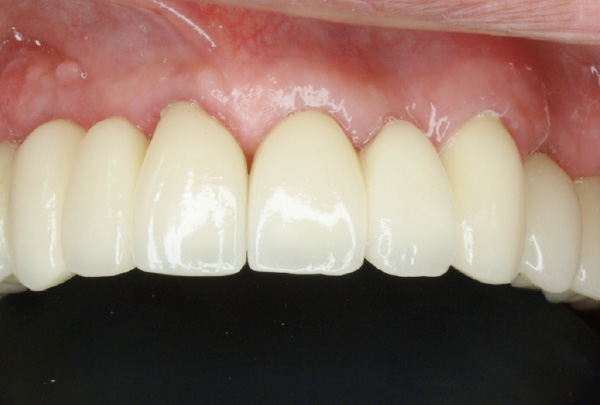

- BEFORE

- AFTER

-